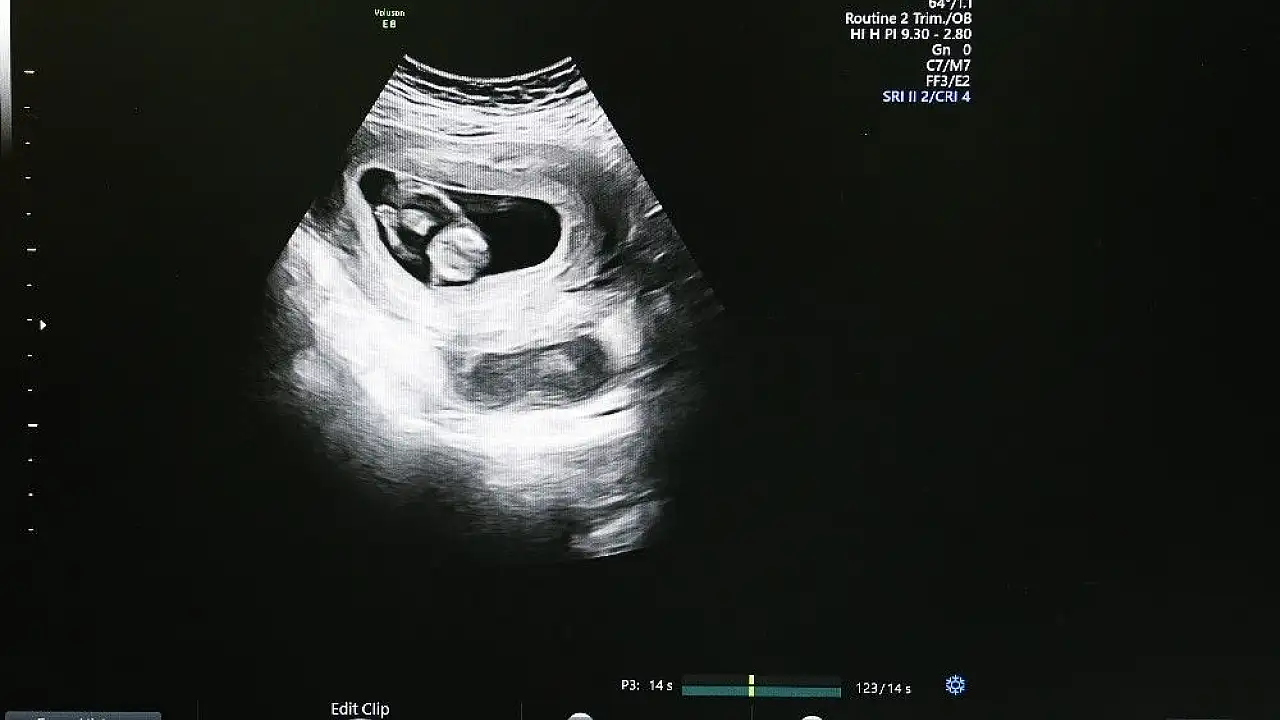

Sivas Cumhuriyet Üniversitesi Araştırma ve Uygulama Hastanesi, riskli gebeliklerin takibini “Ultrasonografi Cihazı” sayesinde kolaylıkla yapılabiliyor.

Sivas Cumhuriyet Üniversitesi Araştırma ve Uygulama Hastanesi, Kadın Hastalıkları ve Doğum Kliniği’nde yaklaşık 1 yıl önce hizmet vermeye başlayan “Ultrasonografi Cihazı” sayesinde anne karnındaki bebeğin bütün yapısal problemleri tespit edilebiliyor.

Konu ile ilgili açıklama yapan Tıp Fakültesi Kadın Hastalıkları ve Doğum Anabilim Dalı Öğretim Üyesi Doç. Dr. Çağlar Yıldız, normal gebeliklerden riskli gebelikler diye tarif edilen üst düzey takip ve tedavi gerektiren tüm gebeliklerin takibini rahatlıkla yapabildiklerini ifade etti. Yıldız, “Riskli gebelik takipleri kliniğimizde üst seviyede yapılabilmektedir. Özellikle bunun için gerekli altyapı konusunda hastanemiz bünyesinde üst düzey ultrasonografi cihazımız mevcuttur ve bu cihazı riskli gebelikler konusunda yaygın olarak kullanmaktayız ” dedi.

Cihaz sayesinde anne karnındaki bebeklerde zor ve güç olan problemleri kolaylıkla görüntüleyebildiklerini anlatan Doç. Dr. Çağlar Yıldız, “Bebeğin vücut yapısında bulunan tüm problemleri tespit edebiliyoruz. Örneğin; kalp, beyin gelişimiyle ilgili problemleri, kol ve bacak, yüz deformiteleriyle ilgili problemleri rahatlıkla ortaya koyabilmekteyiz” şeklinde konuştu.